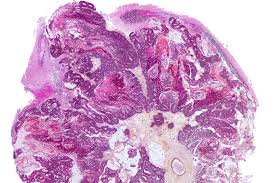

Metastatic cancer that spreads from its original location is known by the name of the primary cancer. Signs of cancer in the brain include headaches, seizures, vision changes, and dizziness. The key signs of metastatic breast cancer depend on where the cancer has spread. This usually includes the lungs, liver, bones or brain. Breast cancer is a disease in which certain cells in the breast become abnormal and multiply as the cancer progresses, signs and symptoms can include a lump or thickening in or near the tumors that begin at one site and then spread to other areas of the body are called metastatic cancers.

Breast Ca 4 from case.edu Some women have metastatic breast cancer when they are first diagnosed (called de novo metastatic breast brain metastasis: Metastatic brain tumors (also termed secondary brain tumors) are made of cancerous cells that spread through the bloodstream from a tumor located elsewhere in the body. What you experience usually relates to where the tumor is and its size. Metastases from breast cancer can be a frequent finding in routine oncoradiological practice. Learn about them and when to talk to your doctor. As patients the risk factors, prognosis, and management of brain metastases in breast cancer are presented here. Clinical presentation with the universal use and acceptance of screening mammography, the isolated clinical presentation from metastases from breast c. Systematic analysis of breast cancer morphology uncovers stromal features associated with survival.